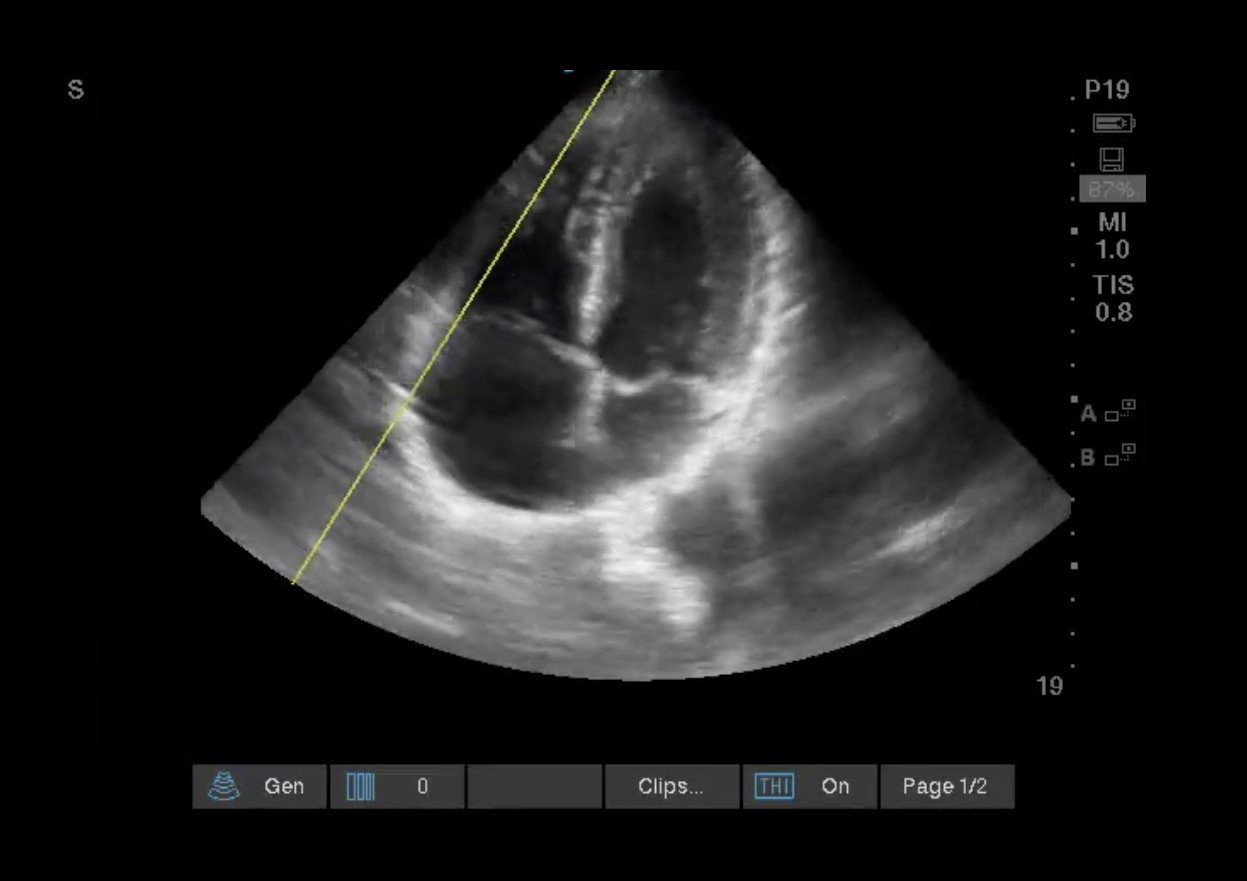

4. 頂部4室:

画像3:正常なRVサイズはLVサイズの⅔以下で、頂部はLVに支配されている

画像4: RVサイズ > LVサイズの⅔ 頂点がRVに支配されている

画像5: McConnellのサイン。 RV自由壁の低運動性と先端部の圧迫感が保たれている。 当初のデータでは、McConnell’s signは、慢性の原発性または二次性肺高血圧症(PHTN)で予想されるより均一な運動低下とは対照的に、急性PEの特異的な指標であることが示唆されていました。 最近のデータでは、PHTNでもMcConnell’s signが見られることから、この結論は否定されている8-9。